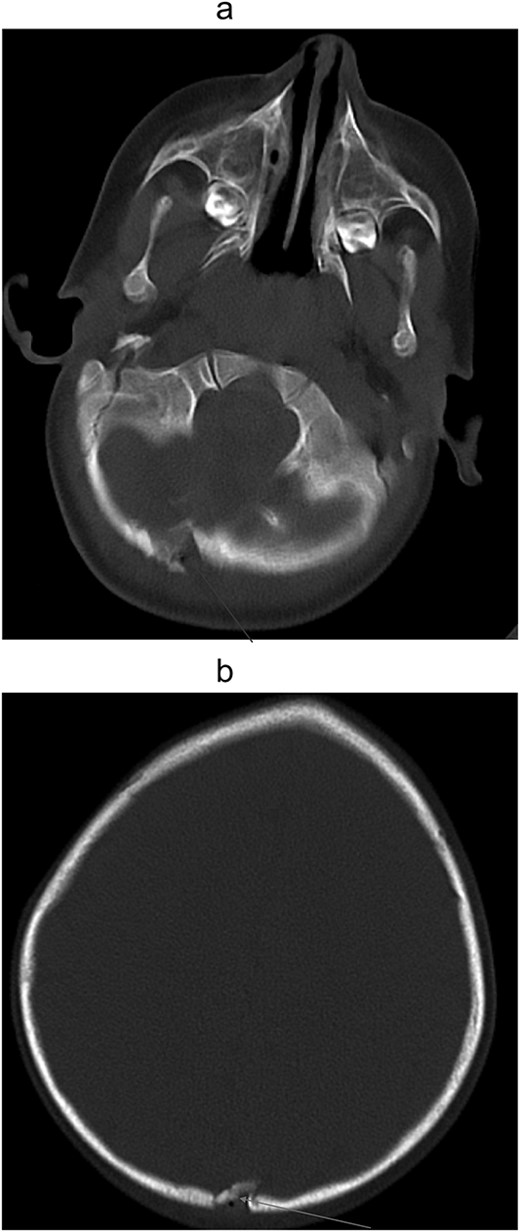

(a) Non-contrast computed tomography of head/brain, sagittal view showing Acute penetrating injury at three sites, with left parietal and occipital scalp laceration and associated depressed comminuted calvarial fractures. Trace extra-axial hemorrhage associated with the fracture of the inferior occipital calvarium and focal edema of the right cerebellar hemisphere, suggesting a small contusion and/or laceration. (b) Noncontract computed tomography of head/brain, sagittal view showing Acute penetrating injury at three sites, with left parietal and occipital scalp laceration and associated depressed comminuted calvarial fractures. Trace extra-axial hemorrhage associated with the fracture of the inferior occipital calvarium and focal edema of the right cerebellar hemisphere, suggesting a small contusion and/or laceration.